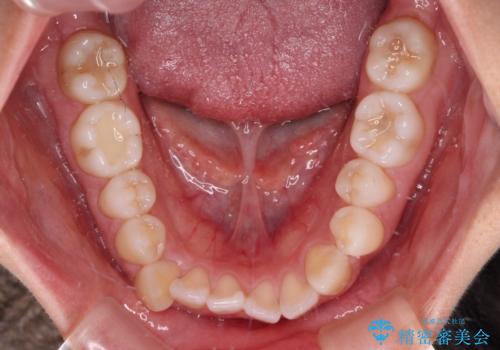

前歯のデコボコを楽して改善 ワイヤー装置による矯正治療

- 前歯のデコボコを治したいとのことで来院された患者様です。

インビザラインによるマウスピース矯正も適用となる歯列でしたが、できる限り楽して、短期間で治したいとのことで、ワイヤー装置にて矯正治療を行うこととしました。